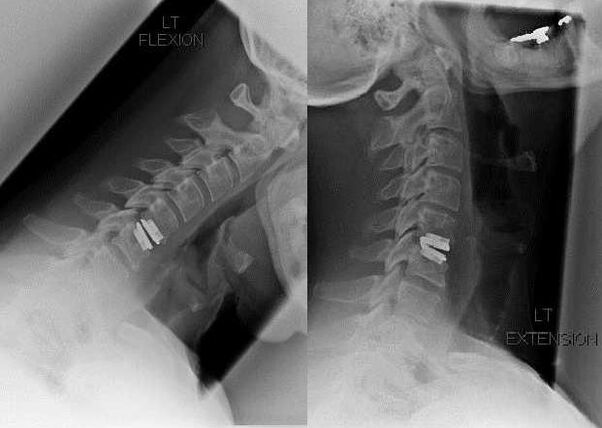

surgical intervention

Indications for surgical intervention include the ineffectiveness of conservative treatment, as well as complications of cervical osteochondrosis, for example, discogenic myelopathy, vertebral artery syndrome and radicular syndrome.To decompress the spinal cord, blood vessels and spinal roots, the following operations are performed:

During surgery, fragments of bone and ligaments may be removed, and intervertebral discs may be completely or partially removed.For small hernial protrusions, laser vaporization of the disc nucleus is often performed.

After excision of vertebral structures, stabilization of the motion segments of the spine by spinal fusion or installation of bone and dermal autografts is often required.